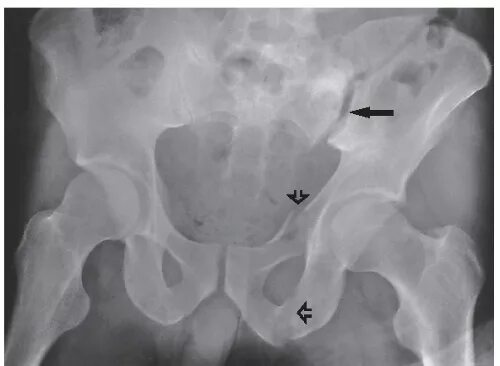

Перелом гребня